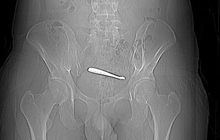

Kết quả chụp CT cho thấy chưa có xuất huyết nội sọ nhưng có chấn thương gan độ II, nghi tổn thương niệu quản phải và bàng quang kèm tụ máu lan rộng khoang sau phúc mạc, tầng sinh môn và đùi phải; gãy phức tạp nhiều mảnh xương mu hai bên và một phần xương cánh chậu phải; tràn dịch màng phổi hai bên.

Ê-kíp tiến hành cầm máu, cắt lọc vết thương, làm hậu môn tạm, mở bàng quang ra da, khâu phục hồi bàng quang, lấy máu tụ và cố định khung chậu gãy.